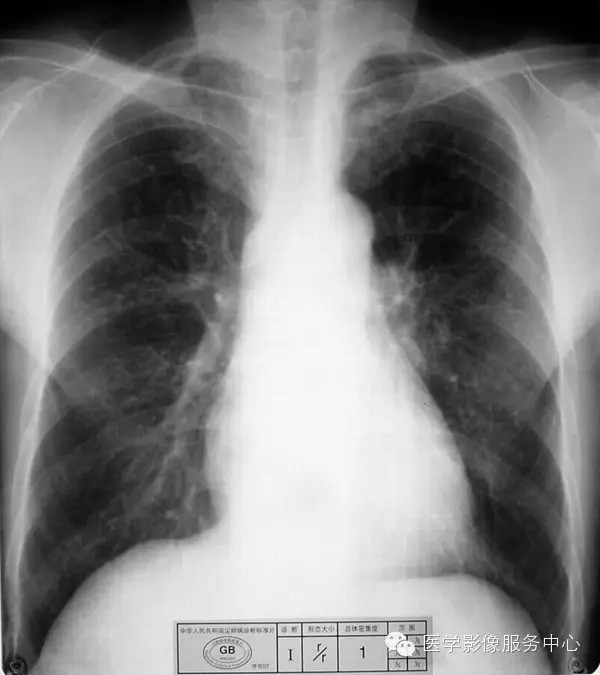

4.2 一期尘肺(Ⅰ)

a)Ⅰ:有总体密集度1级的小阴影,分布范围至少达到两个肺区。

b)Ⅰ :有总体密集度1级的小阴影,分布范围超过4个肺区或有总体密集度2级的小阴影,分布范围达到4个肺区。